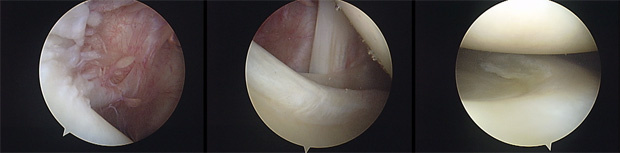

Após a avaliação do espaço articular, reposicionamos o artroscópio para avaliar o espaço subacromial. Nesse local, podemos identificar patologias da bursa subacromial, do manguito rotador, do acrômio, do ligamento coracoacromial e da articulação acrômioclavicular.

Apresentamos, a seguir, vídeos de procedimentos artroscópicos para bursectomia e acromioplastia, realizados em pacientes com Síndrome do Impacto Subacromial.